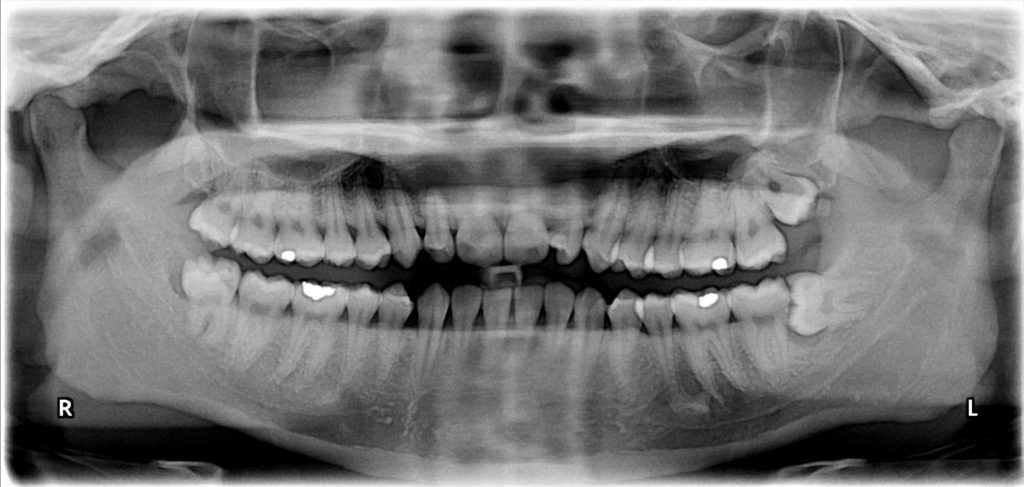

Подвывих вправляется врачом в большинстве случаев руками после внешнего осмотра и рентгеновского снимка. Силовое вправление челюсти проводит ортодонт, хирург или травматолог. Часто врач применяет общую или местную анестезию, так как методика причиняет острую боль. Покой суставу затем обеспечивается при помощи плащевидной повязки.

Врачи категорически запрещают вправлять челюсть самостоятельно, так как без профессионального обследования, рентгеновского снимка нельзя определить, вывих у вас или перелом челюсти.